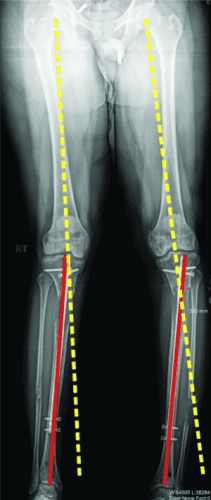

敲击(外翻)鞠躬(内翻)

屈曲(procurvatum)

在外部机构胫骨身材延长并出现双侧并发症的患者。他发展了胫骨和 Abu/a 延迟结合,右侧是敲击 {外翻),左侧是弓形 {内翻),两侧是 f1exion {procurvatum}。我们在手术室使用临时外部斧头机对两侧进行了急性矫正,并放置了新的胫骨杆。我们在 Abu/a 延迟结合上放置了逆行杆。